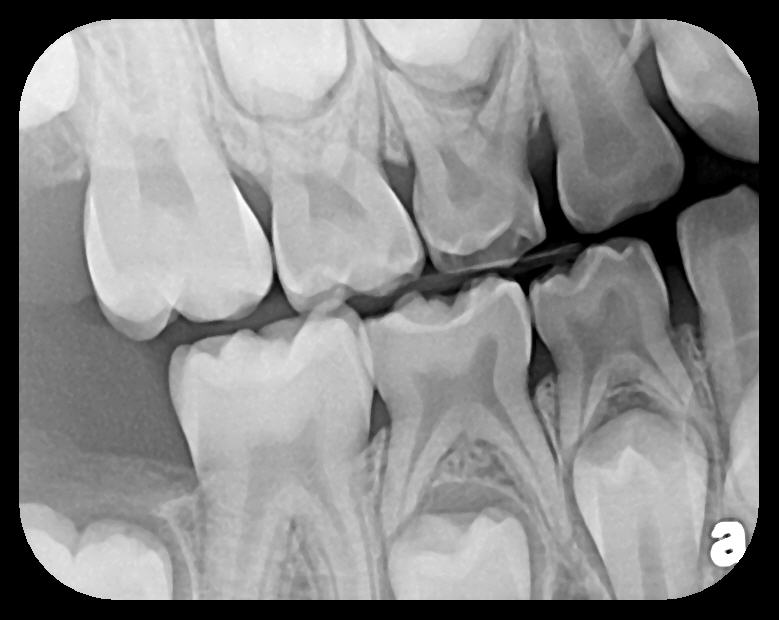

Fig 3. Two PSP PA radiographs of mandibular teeth showing: left, the initial view

of molar area and suspected pathology surrounding impacted tooth No. 32; center,

subsequently exposed PA radiograph, placed more distally, demonstrates extent

of large cyst as well as entire tooth and root No. 32. Proper alert as to presence

of suspected cyst and appropriate referral for 3D CBCT study and surgical

enucleation was given to the patient. Right: Same radiograph as on the left, but

with lighter superimposed outline of the area that would be visible using an HW

sensor rather than a PSP sensor. The small area of pathology is likely obscured

because it is visually overlaid by the root of tooth No. 31. Neglect of this significant

pathology may have resulted.

Figure 3